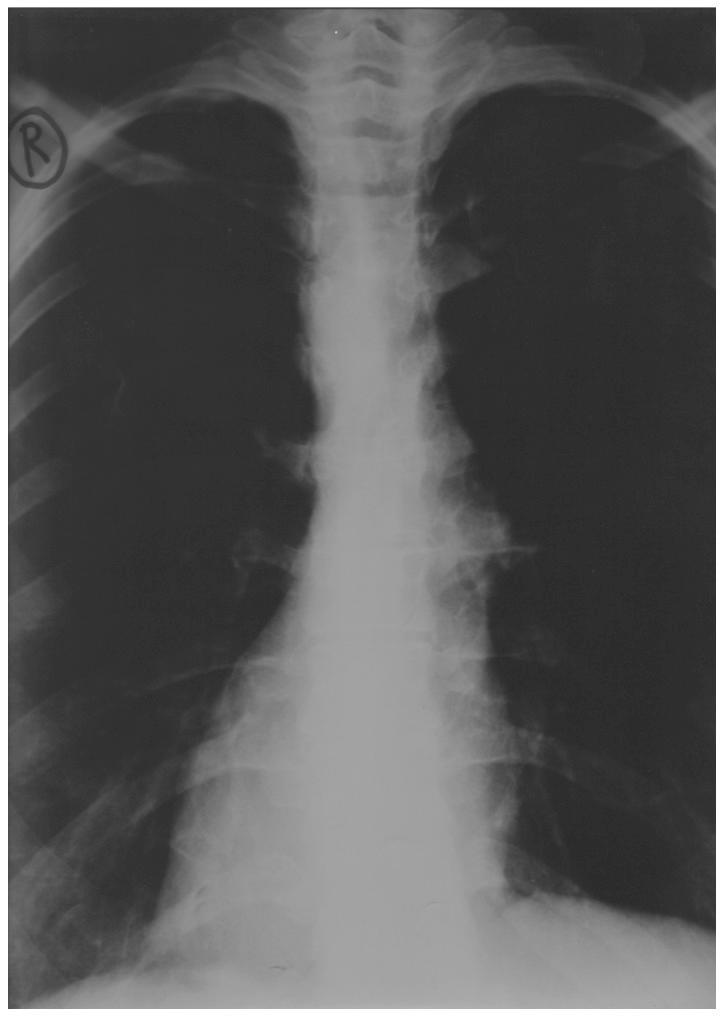

Situs inversus is a rare congenital anomaly in which the organs are transposed from their normal site to the opposite side of the body. To the best of our knowledge, this is the first study of staging laparotomy performed in a patient with endometrial carcinoma and situs inversus totalis (SIT). This study presents a patient with early endometrial carcinoma with SIT who underwent staging laparotomy. Total abdominal hysterectomy with bilateral salphingoophorectomy, omentectomy and pelvic para-aortic lymph node dissection was successfully performed without additional blood loss and time. The number of retrieved lymph nodes was 47. No abnormal course of blood vessels except for the right/left inversion was found. The postoperative course was favorable and the patient was discharged eight days after surgery.

内脏反位是一种罕见的先天性异常,其中器官从其正常位置转移到身体的另一侧。据我们所知,这是首例针对患有子宫内膜癌和完全性内脏反位(SIT)的患者进行分期剖腹手术的研究。本研究报告了一名患有早期子宫内膜癌合并SIT的患者接受了分期剖腹手术。成功实施了全腹子宫切除术、双侧输卵管卵巢切除术、大网膜切除术和盆腔及腹主动脉旁淋巴结清扫术,未出现额外失血且手术时间正常。获取的淋巴结数量为47个。除左右反位外,未发现血管走行异常。术后恢复顺利,患者术后8天出院。